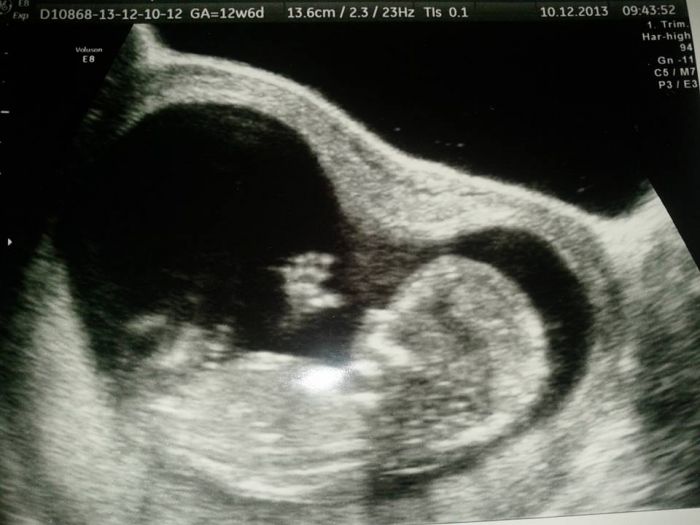

Ahojky holky, tak konečně jsem se sem dostala (je to nějaký hektický posledních pár dní

), abych se mohla pochlubit, že jsme v úterý na screeningu dopadli dobře a přikládám fotečku. Prcek byl akční a mával na nás, přikládám fotečku...akorát pohlaví nám pan doktor neřekl, že by to ještě nechal otevřený...tak uvidíme...